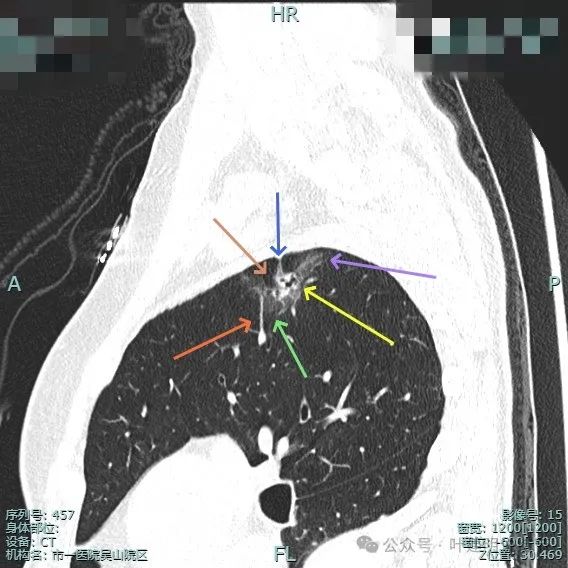

此视角看是典型的浸润性腺癌影像表现:混合密度、毛刺锐利典型、表面分叶、边缘不平、灶内实性成分明显且整体显得杂乱、病灶内部明显扩张的细支气管,磨玻璃成分与正常肺组织之间边界清楚,整体轮廓也清楚。

实性成分较明显,扩张的支气管壁显得僵硬,表面分叶明显,边缘细毛刺明显。

毛刺征、混合密度且实性成分杂乱、支气管扩张僵硬、分叶征明显。

血管进入、表面分叶、胸膜牵拉、磨玻璃成分明显、实性部分缺乏收缩力但显杂乱,整体轮廓与边界清。